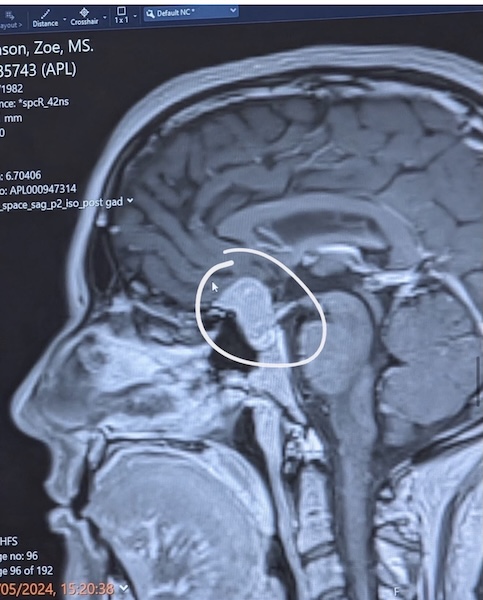

If you are reading this and something in your body feels “off,” trust that instinct. Ask the extra question. Push for answers. You are not overreacting. The meningioma is behind my right eye. I’ve lost sight, colour vision, and balance. I have daily headaches, restless leg syndrome and so much more.